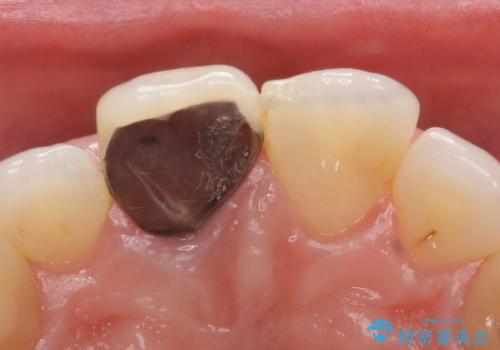

- 右上1の前歯の見た目が気になるので被せ物をやり替えたいといらっしゃった方の症例です。

再根管治療終了後、オールセラミッククラウン(スペシャル)によって隣在歯に合わせた補綴を行いました。